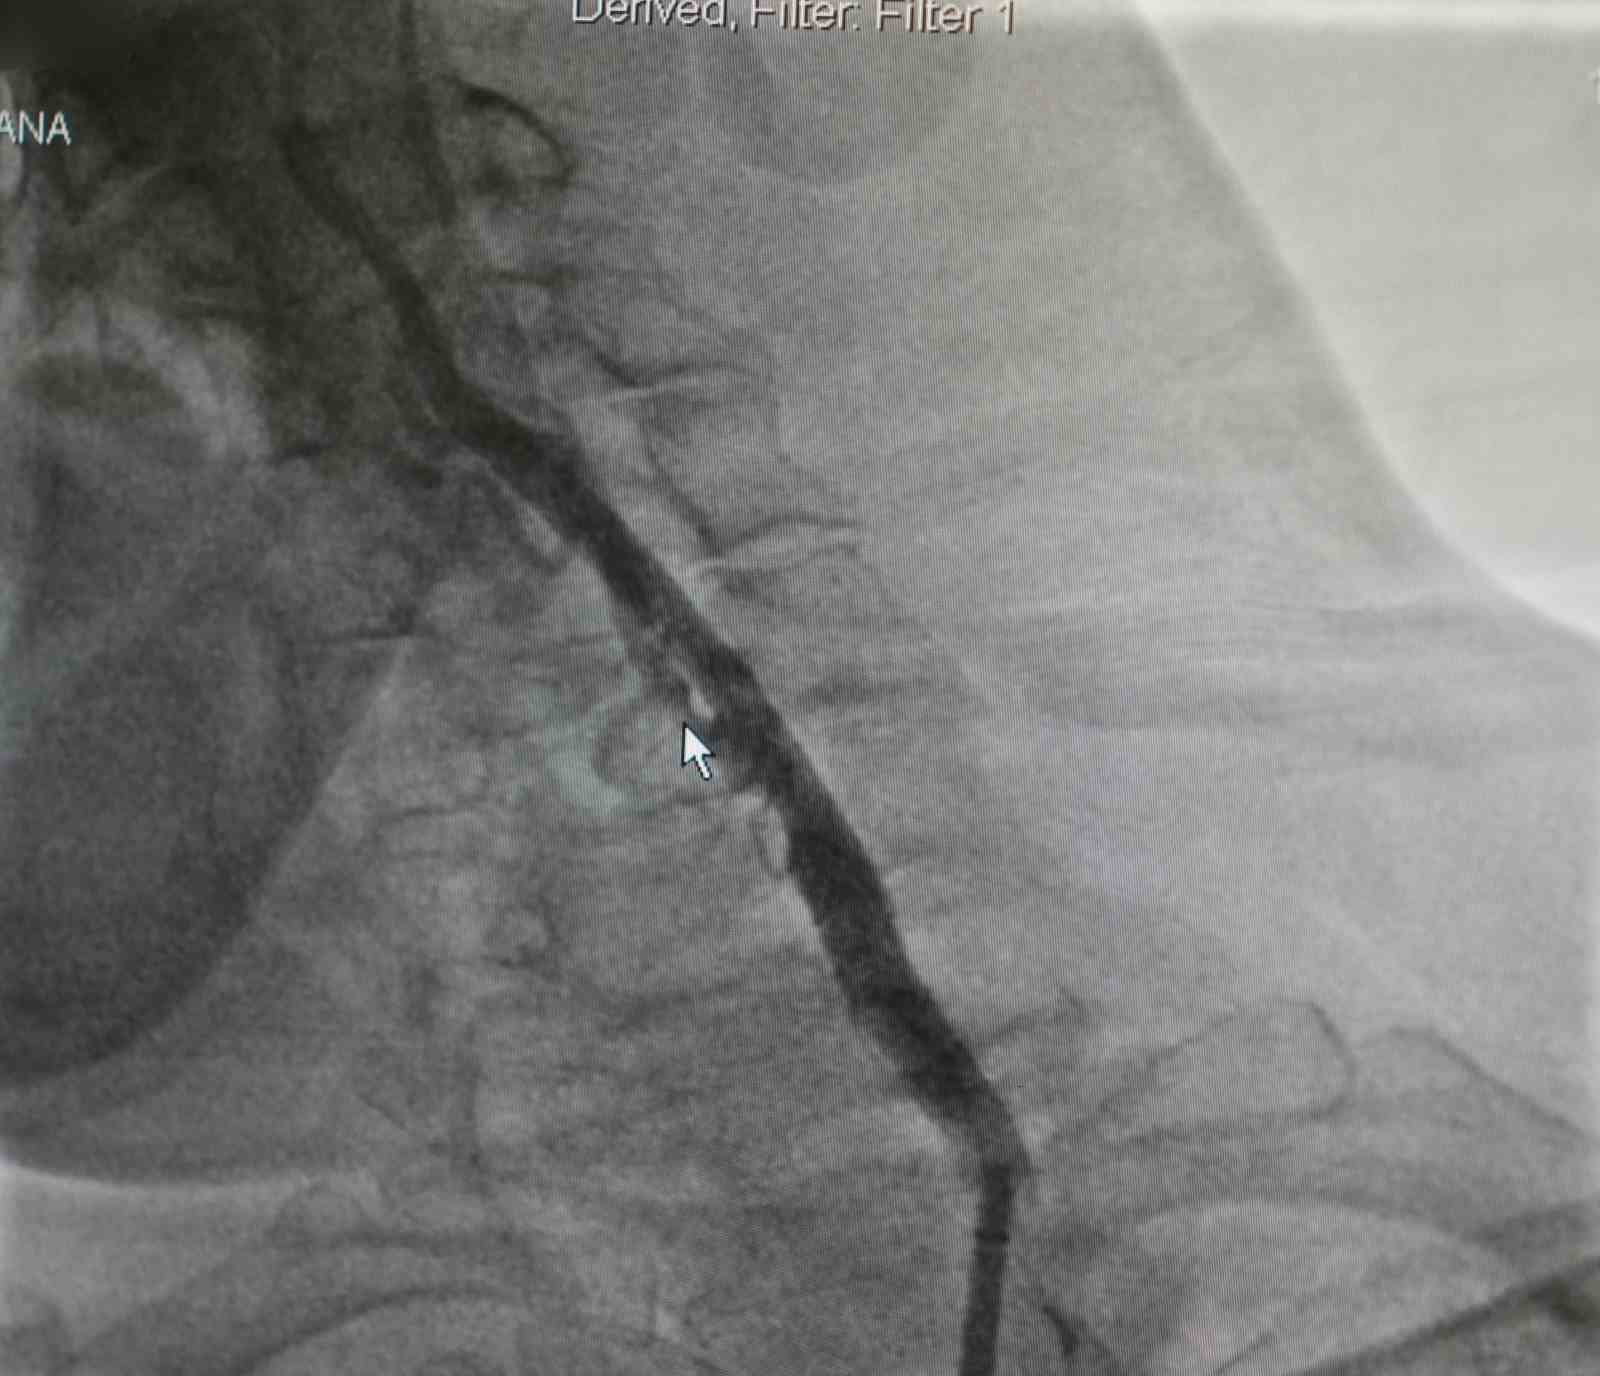

Samsun’da yaşayan Zekai Bozyel (71), 15 yıl önce bypass ve kalp kapak ameliyatı geçirdi. Rutin kontrolleri devam eden Bozyel, 20 gün önce kolunda güçsüzlük şikayetiyle nöroloji servisine yatırıldı. Yapılan tetkiklerde hastanın sağ boyun damarında yüzde 30, sol boyun damarında ise yüzde 90 oranında darlık tespit edildi. Sol taraftaki ciddi darlığın hastanın felç geçirmesine neden olduğu belirlendi. Hastanın daha önce kronik akciğer rahatsızlığı bulunması ve geçirdiği ameliyatlar nedeniyle anestezi açısından yüksek risk taşıdığı değerlendirildi. Bunun üzerine hastanın durumu kardiyoloji ekibi tarafından yeniden ele alındı. Akabinde Medicana International Samsun Hastanesi Kardiyoloji Uzmanı Dr. Öğr. Üyesi Ahmet Yanık, boyun damarında yüzde 90 darlık tespit edilen ve daha önce baypas ile kalp kapak ameliyatı geçiren hastaya ameliyatla kasıktan girerek uygulanan anjiyografik yöntemle stent yerleştirdi. Gerçekleştirilen başarılı müdahaleyle yeniden felç riskinin önüne geçildiğini belirtti.

Hastanın filmlerini inceleyip muayenesini yaptıklarını belirten Dr. Öğr. Üyesi Ahmet Yanık, "Zekai bey 15 yıl önce bypass ve kalp kapak ameliyatı olmuş, rutin takiplerinde devam eden bir hastamız. 20 gün önce nöroloji servisine yatıyor. İnme hikayesi ve kolunda güçsüzlük var. Yapılan tetkiklerinde boyun damarında darlık saptanıyor. Sağdaki boyun damarında yüzde 30, soldaki boyun damarında ise yüzde 90 civarında bir darlık var. Bu felç geçirmesine sebep olan bir darlık. Öncelikle ameliyat düşünüldü ancak kronik akciğer öyküsü ve diğer rahatsızlıkları nedeniyle anestezi açısından riskli bulundu. Biz damarın bu şekilde bırakılmasının daha riskli olacağını düşündük. Hastamızla görüşerek işlemi yapmaya karar verdik. Başarılı bir şekilde soldaki boyun damarına kasıktan girerek, herhangi bir kesi yapmadan anjiyografik olarak stent yerleştirdik. İşlem sonrası herhangi bir sorun yaşamadık ve hastamızı taburcu ettik. Müdahale edilmemesi durumunda daha ciddi bir felç riski söz konusuydu" dedi.